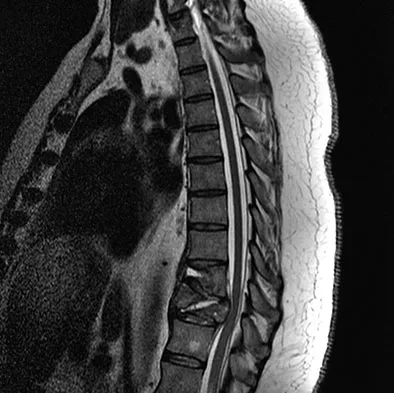

A 50-year-old man with no history of trauma reports new-onset back pain after doing some yard work the previous day. He reports pain radiating down his leg posteriorly and into the first dorsal web space of his foot. MRI scans are shown in Figures 3a through 3c. What nerve root is affected?

A 42-year-old man with a history of renal cell carcinoma has progressive weakness in the lower extremities for the past 3 weeks. The patient desires intervention. A sagittal T2-weighted MRI scan is shown in Figure 9a, and a sagittal contrast enhanced T1-weighted MRI scan is shown in Figure 9b. He currently ambulates minimal distances with a walker. His life expectancy is 8 months. Treatment of the spine lesion should consist of